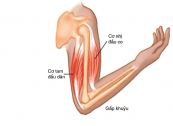

Nếu bắp tay, vai hoặc khuỷu tay bạn bị đau, sưng, khó vận động thì rất có thể bạn đã rơi vào tình trạng chấn thương cơ nhị đầu cánh tay. Vậy nguyên nhân và triệu chứng của tihf trạng này là gì? Làm thế nào để điều trị và phòng ngừa bệnh hiệu quả? Tham khảo bài viết dưới đây để hiểu rõ hơn nhé!